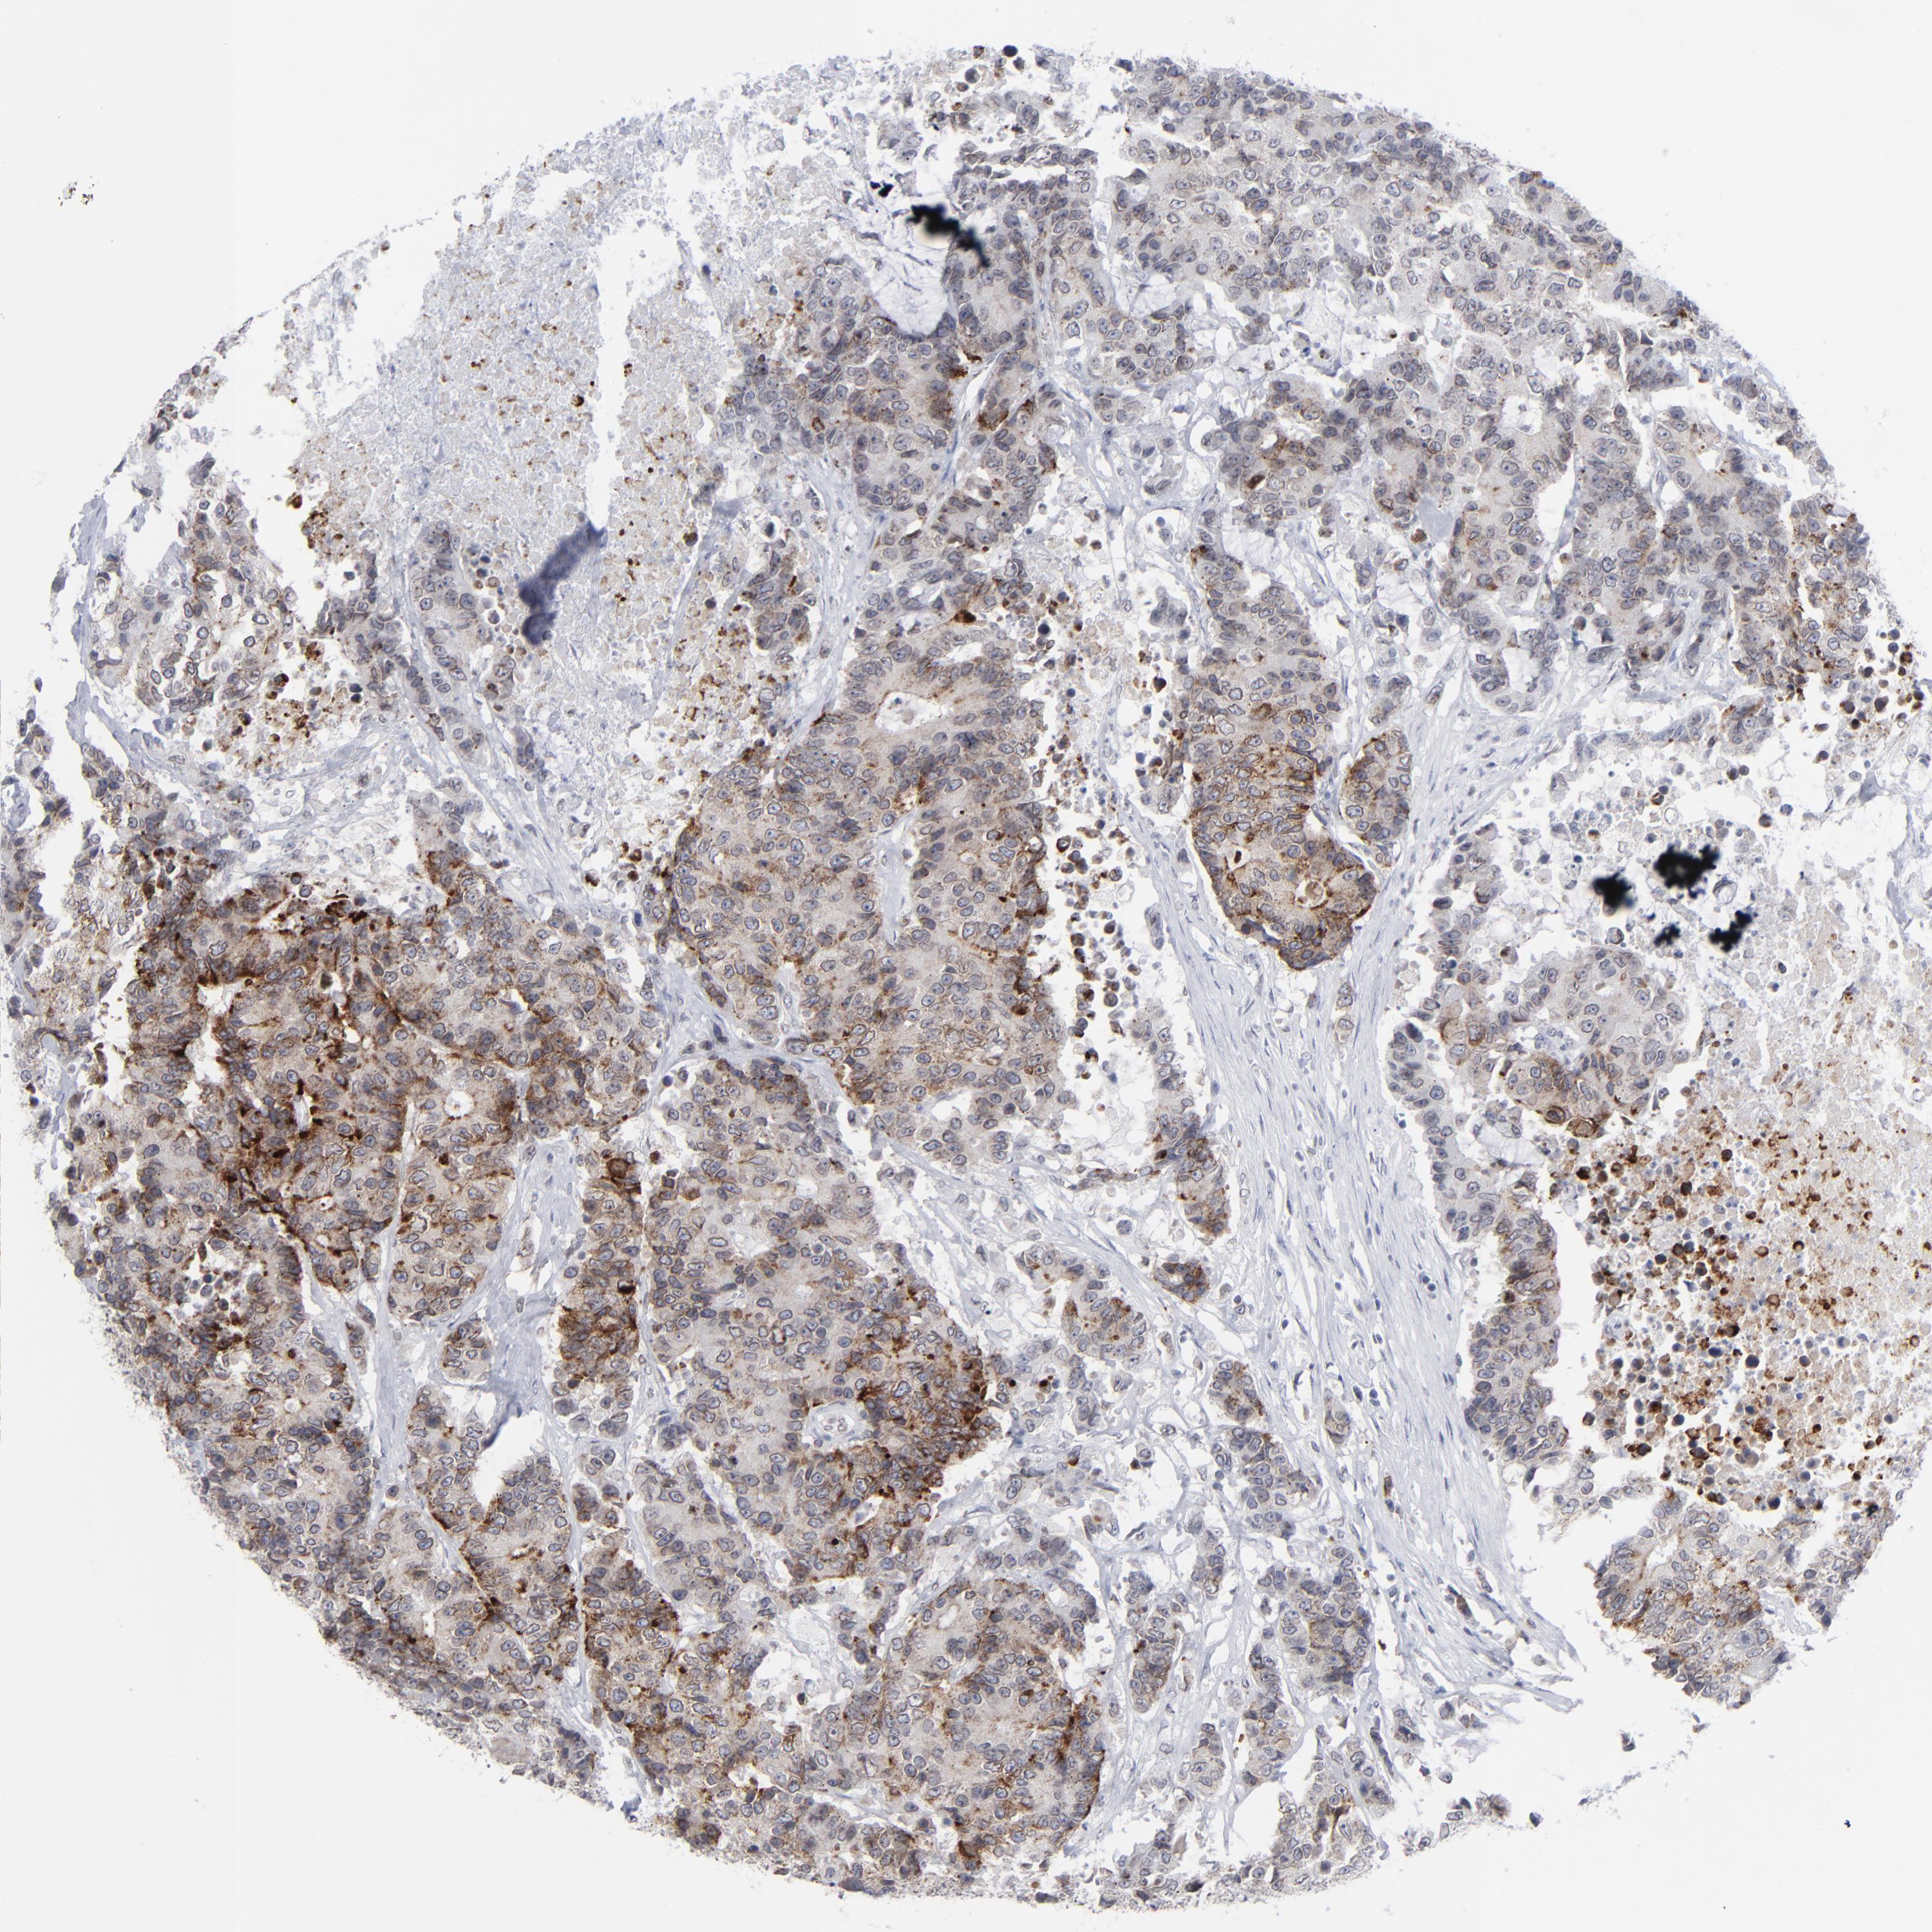

ANTIBODIES

AND

VALIDATION